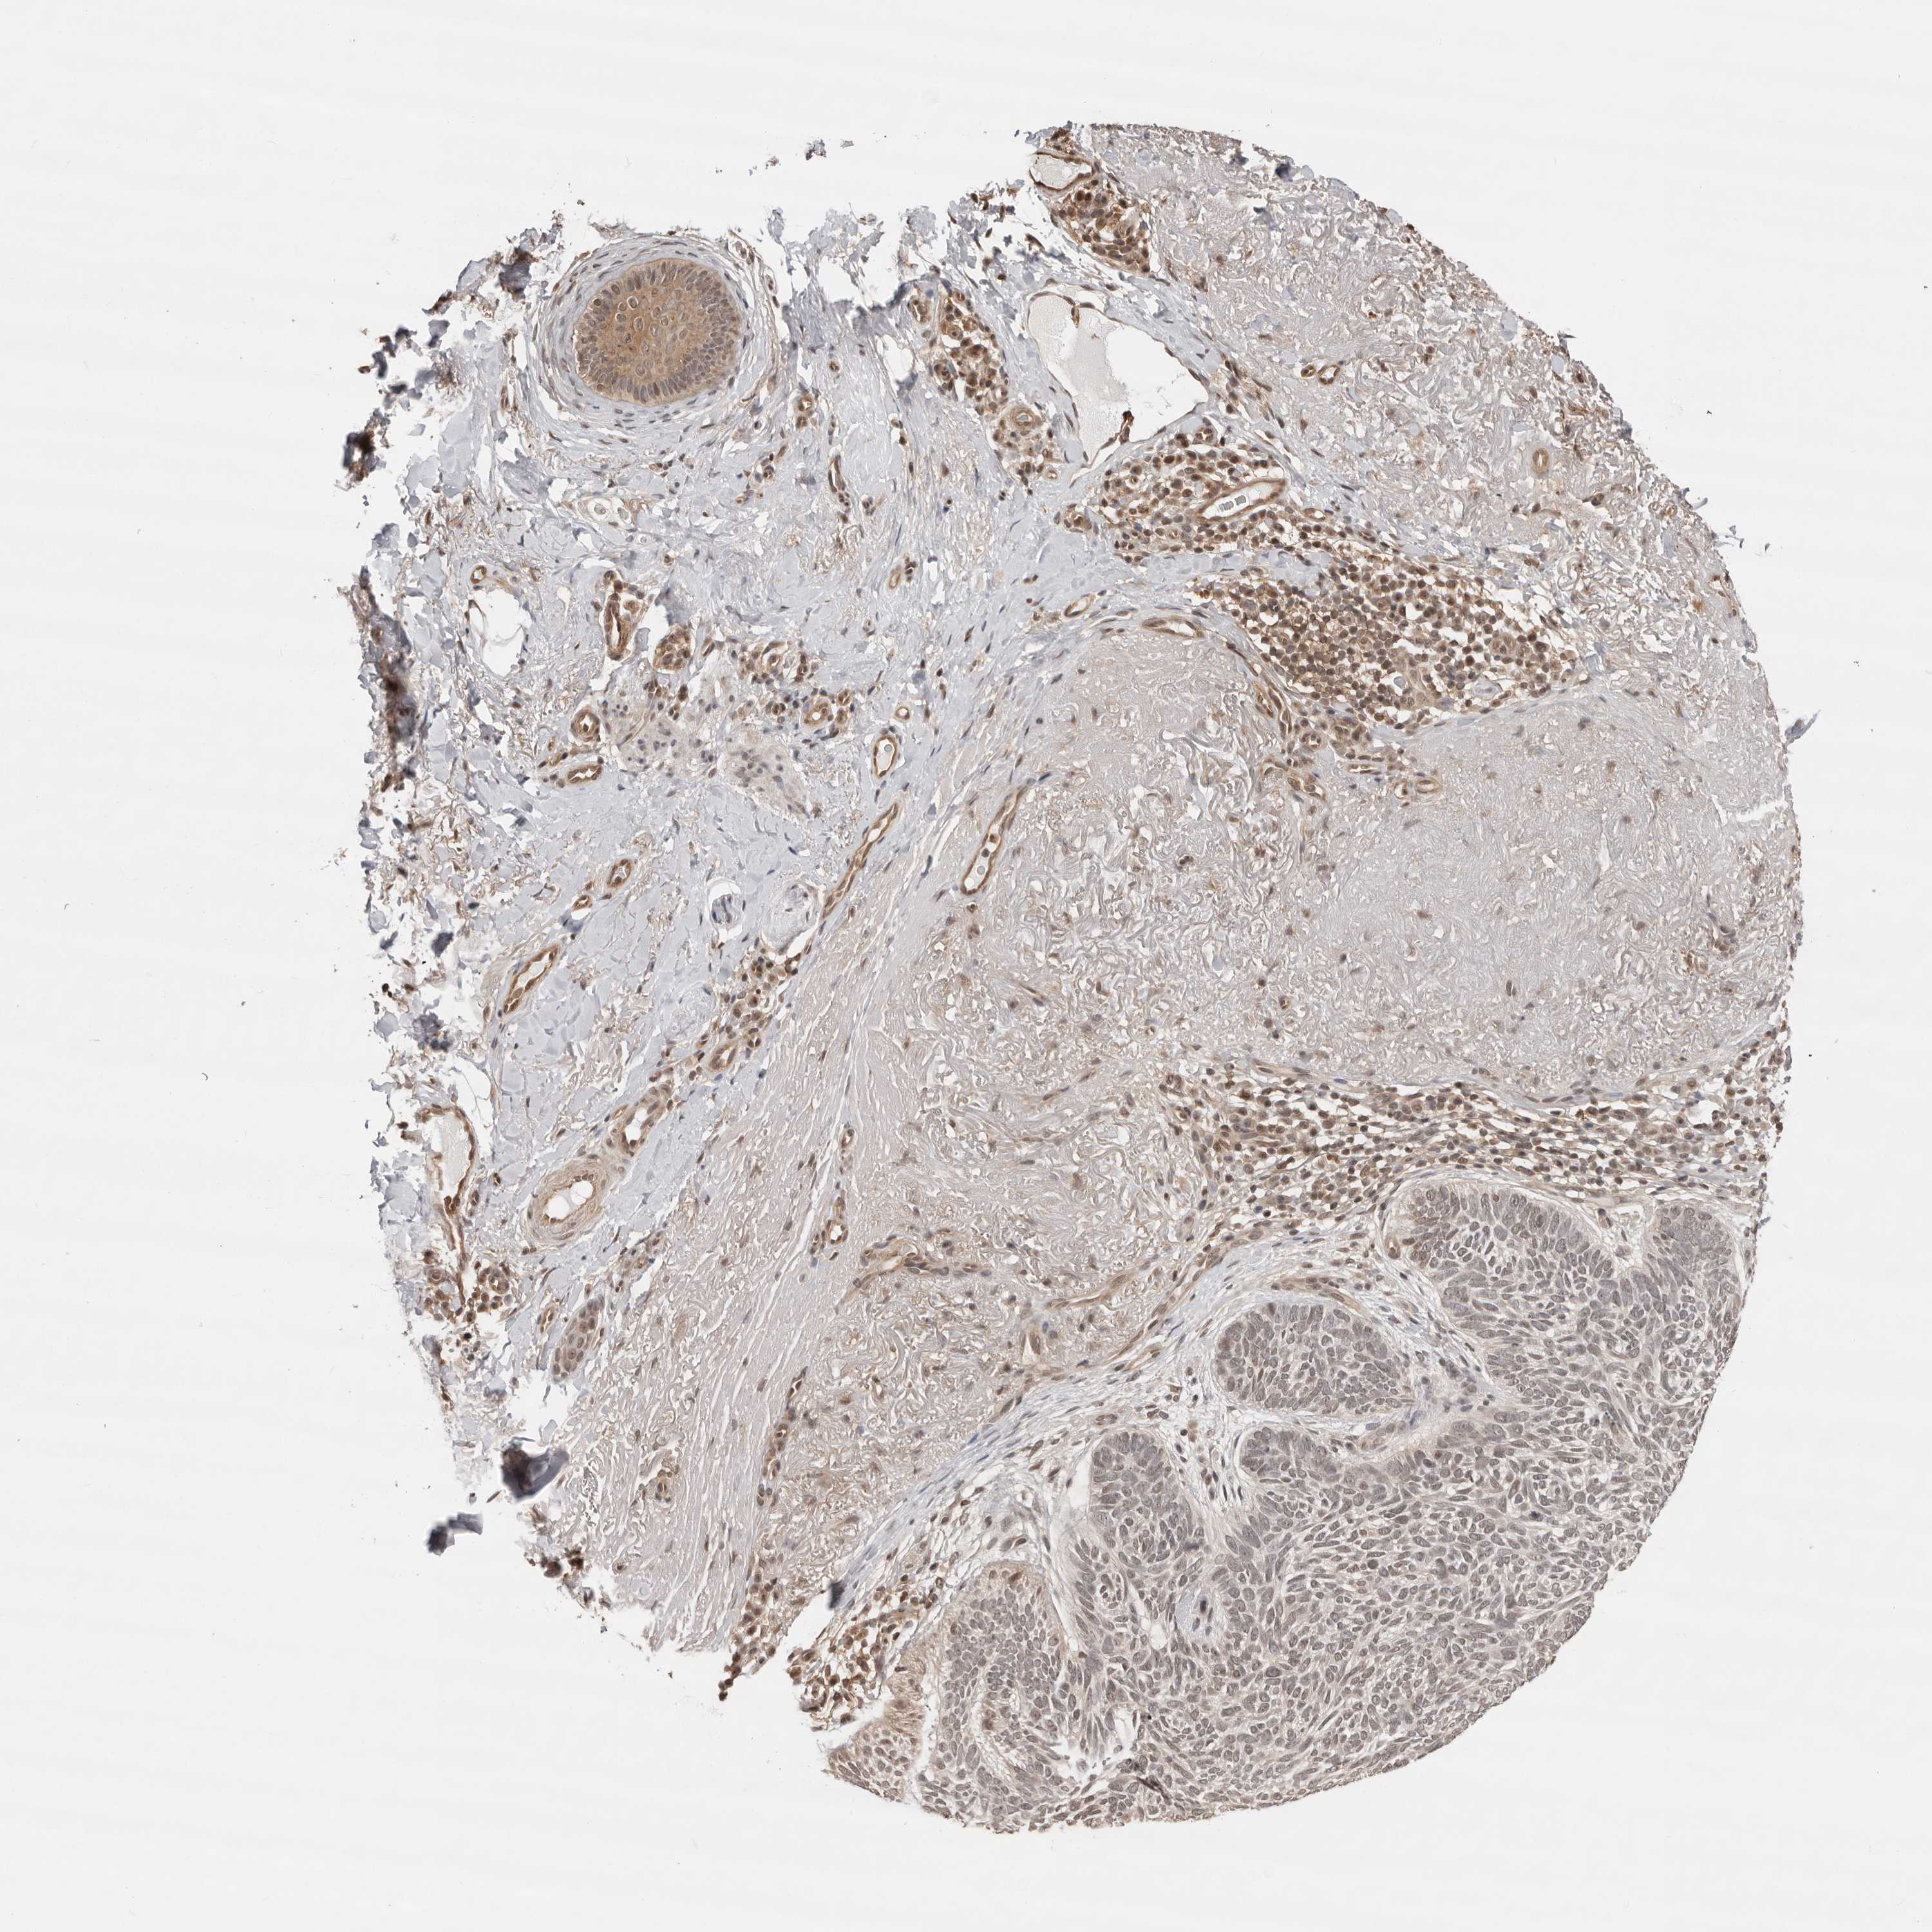

Basal cell and squamous cell cancer

SKIN CANCER - Protein expressioni

A mouse-over function shows sample information and annotation data. Click on an image to view it in a full screen mode. Samples can be filtered based on level of antibody staining by selecting one or several of the following categories: high, medium, low and not detected. The assay and annotation is described here.

Antibody stainingi

Antibody staining in the annotated cell types in the current human tissue is reported as not detected, low, medium, or high, based on conventional immunohistochemistry profiling in selected tissues. This score is based on the combination of the staining intensity and fraction of stained cells.

Each image is clickable and will lead to virtual microscopy that enables deeper exploration of all samples and also displays staining intensity scores, fraction scores and subcellular localization as well as patient and tissue information for each sample.

Antibody HPA028467

Staining

High

Medium

Low

Not detected

Intensity

Strong

Moderate

Weak

Negative

Quantity

>75%

75%-25%

<25%

None

Location

Nuclear

Cytoplasmic/membranous

Cytoplasmic/membranous,nuclear

Basal cell carcinoma